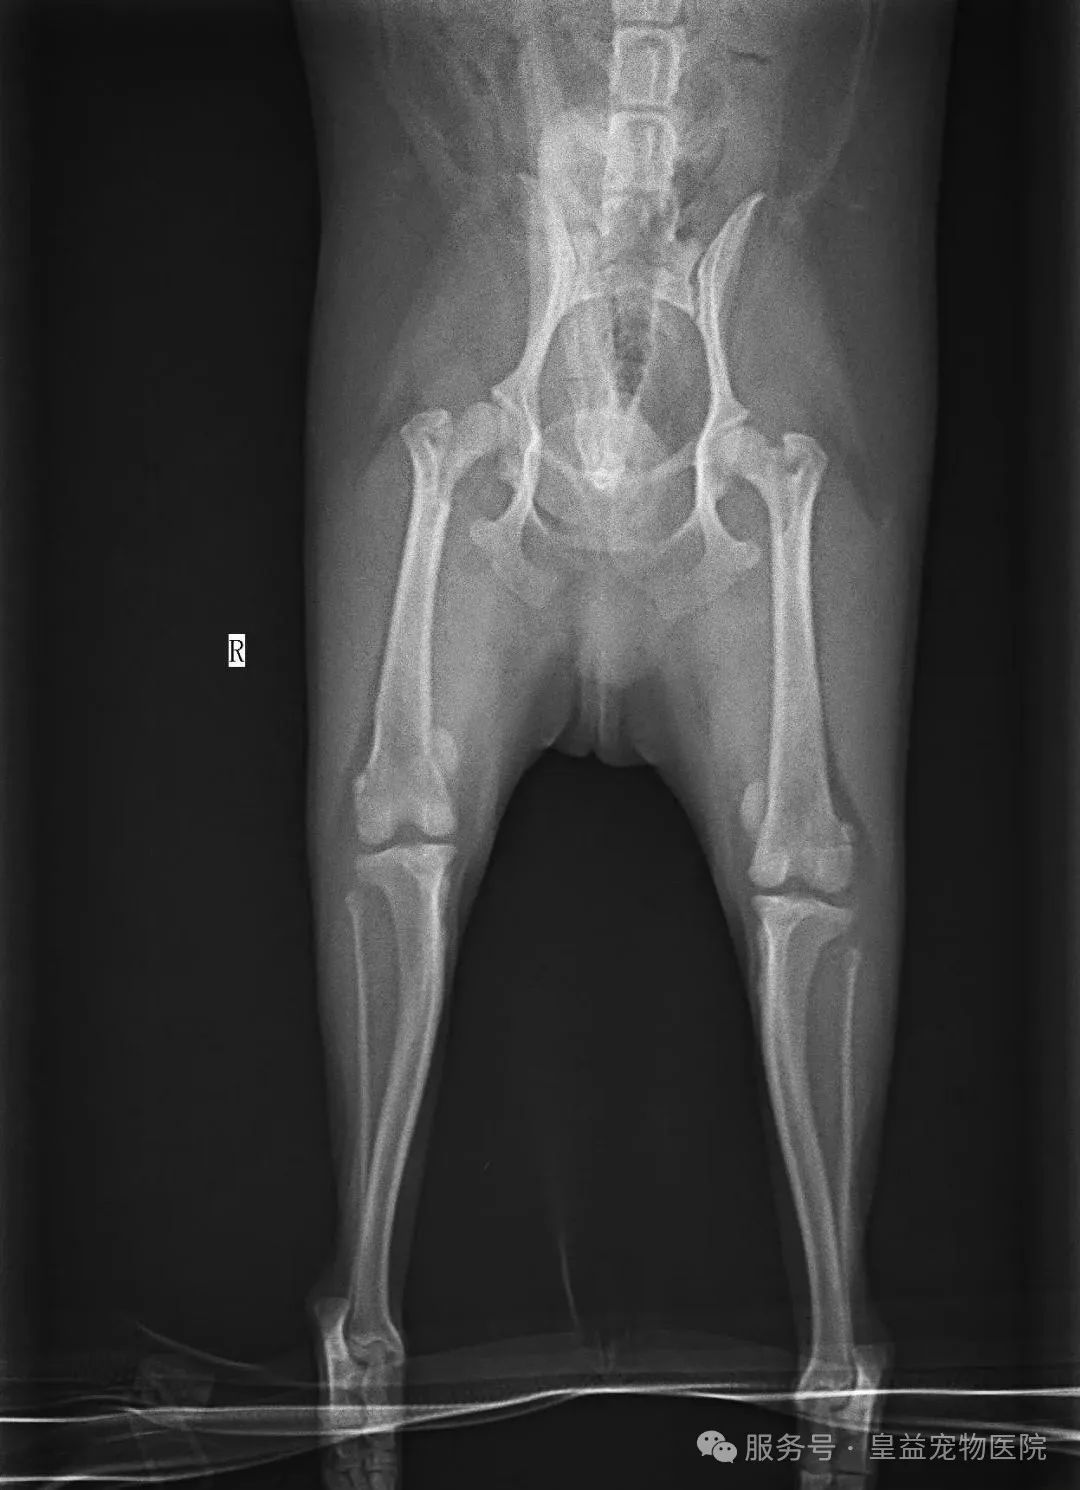

3级(中重度)

- 髌骨大部分时间处于脱位状态,需手动复位,但松手后很快再次脱出。

- 狗狗持续跛行,患肢无法正常伸直,可能出现肌肉萎缩。

- 关节变形风险增加,可能影响十字韧带和半月板。

4级(重度)

- 髌骨**性脱位,无法手动复位。

- 患肢严重变形,胫骨可能旋转60°~90°,狗狗可能拖行后腿或瘫痪。

- 需手术治疗,保守治疗无效。